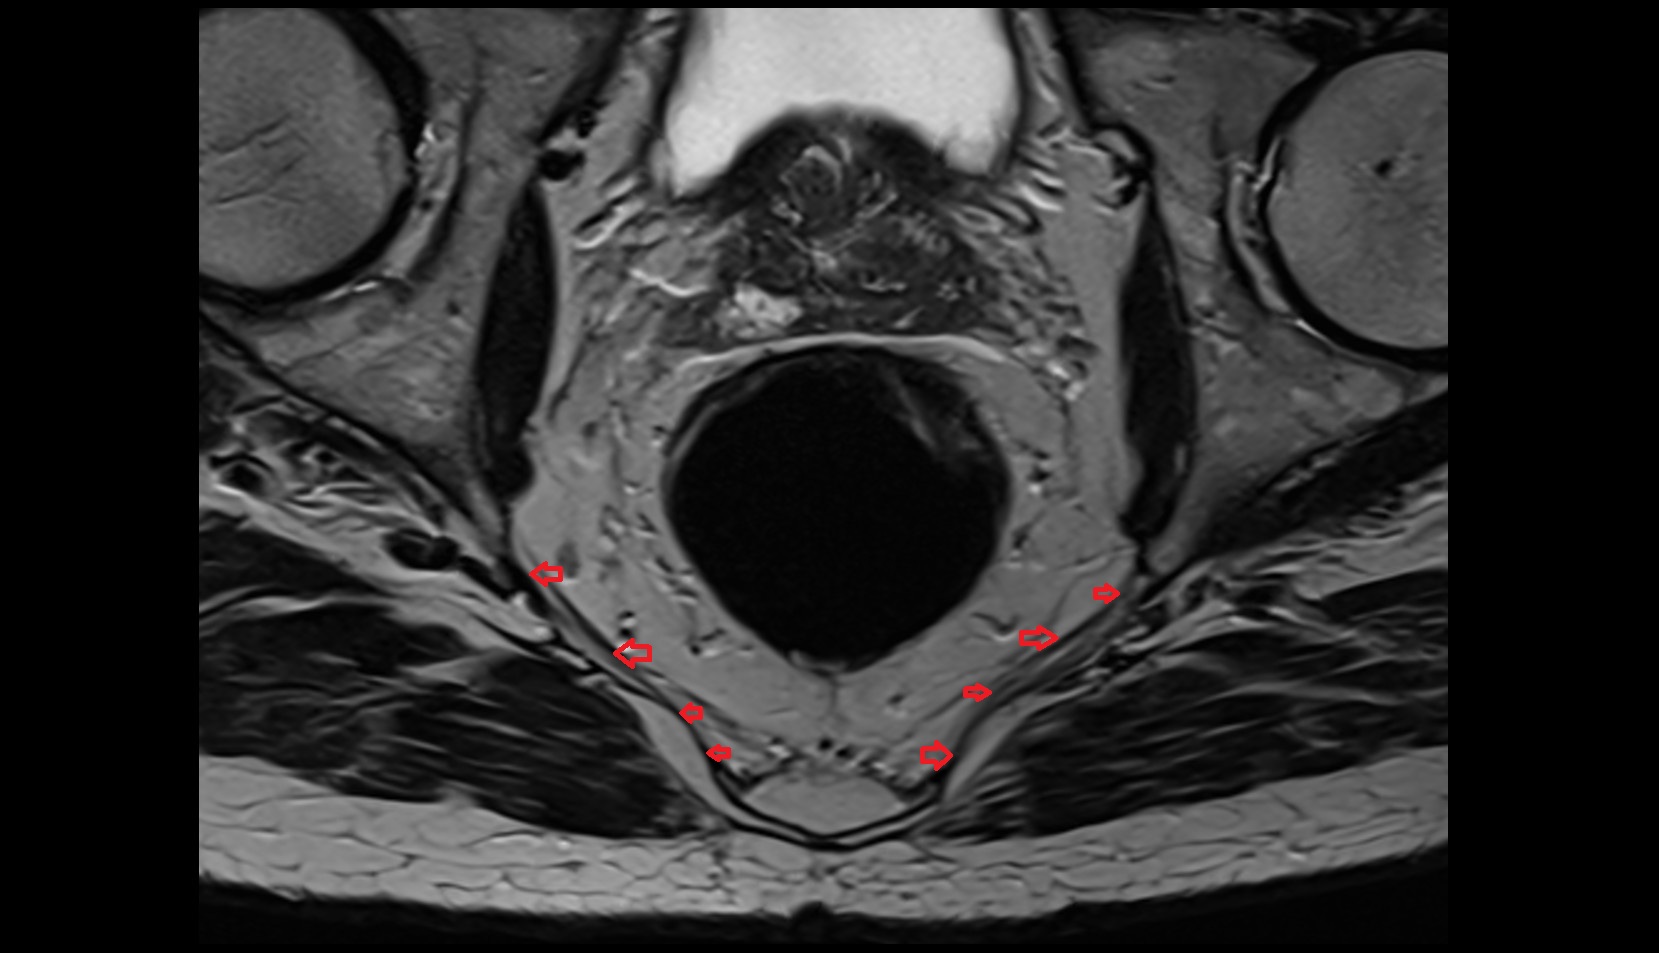

- Mesorectal fascia

- Rectum

- Levator ani muscle

- Peripheral zone of prostate